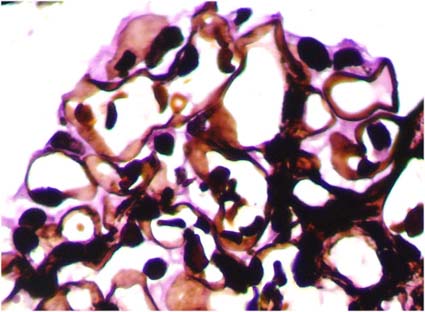

The mesangial matrix is formed by different types of collagen (III, IV, V and VI), microfibrillar proteins, glycoproteins, proteoglycans and other components (Venkatachalam MA, Kriz W. Anatomy (of the kidney). In Heptinstall's Pathology of the Kidney, Lippincott-Raven, Philadelphia, 1998, pp. 3-66) (Figure 4 and Figure 5).

Figure 4. The mesangial matrix, like the basement membranes of capillaries, Bowman’s capsule, and tubules are rich in type IV collagen, and has affinity by the methenamine-silver stain. See the irregular characteristic aspect of mesangial matrix (in black) in a normal glomerulus (Methenamine-silver, X.400).